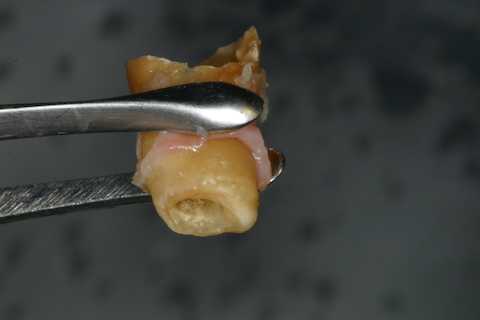

今日の抜歯再植術シリーズ39.2 2025.11.15